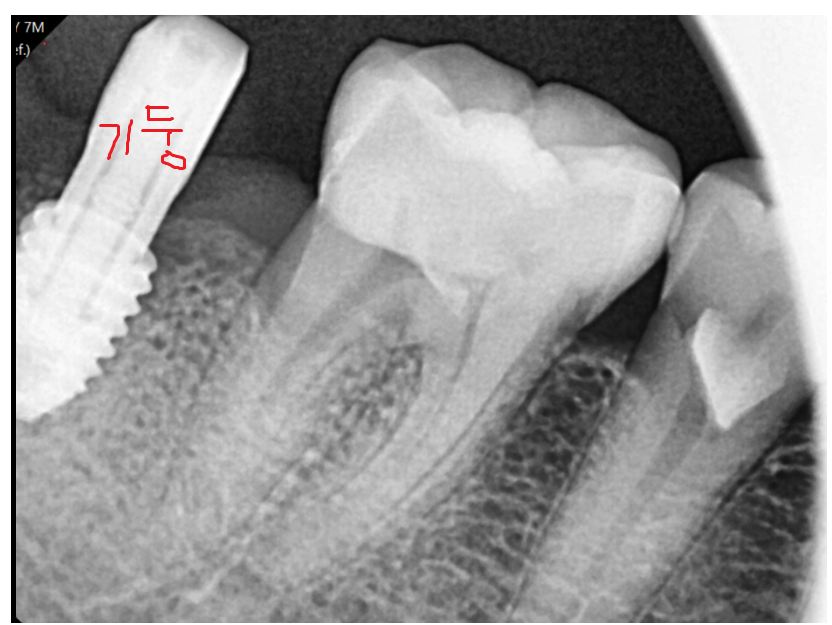

240622

안정적인 상황에서

머리를 만들어드리는 과정을 진행해드렸고

240720

문제의 치아 해결해드렸기에

이제 씹을 때마다 통증

안녕~~